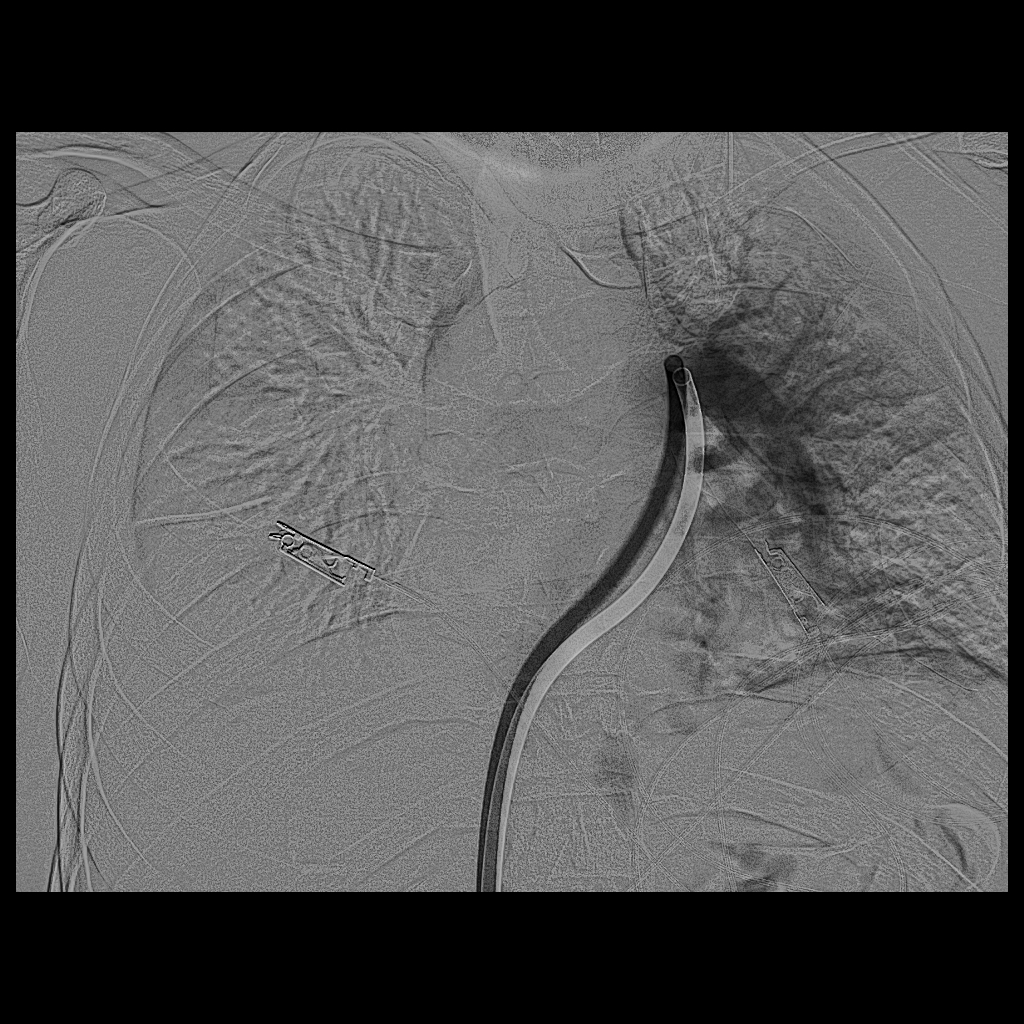

سجل مجمع الدمام الطبي أحد مكونات تجمع الشرقية الصحي ، إنجازاً طبياً نوعياً بعد نجاح فريق الأشعة التداخلية في إنقاذ حياة مريض كان يعاني من جلطة رئوية حادة وكبيرة شكّلت خطراً مباشراً على حياته ، وذلك باستخدام تقنية طبية متقدمة دون الحاجة إلى جراحة قلب مفتوح .

وكان المريض قد نُقل بشكل إسعافي من أحد المستشفيات وهو في حالة حرجة ، نتيجة معاناته من ضيق شديد في التنفس وانخفاض حاد في مستوى الأكسجين ، إثر انسداد كامل في الشريان الرئوي الرئيسي بسبب خثرات وريدية عميقة ظهرت بعد خضوعه لعملية منظار لمفصل الركبة.

وبفضل سرعة الاستجابة وجاهزية فريق الأشعة التداخلية جرى التدخل العلاجي العاجل وفتح الشريان الرئوي وسحب الجلطة بالكامل بدقة عالية ، ما أدى إلى تحسّن فوري في العلامات الحيوية واستقرار الحالة دون تسجيل أي مضاعفات.